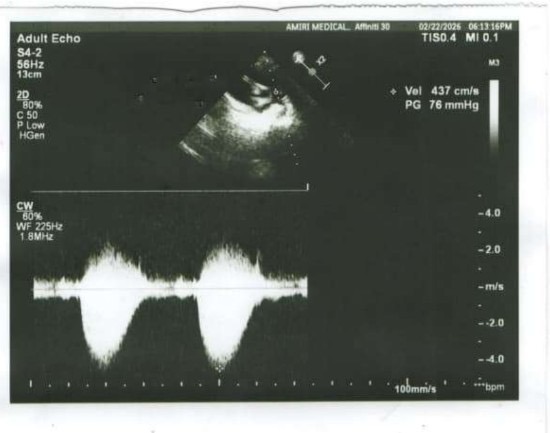

His case is urgent but it is treatable. Little Emad is two and a half years old. He loves playing outside and toy cars. He also has been diagnosed with a congenital heart condition called Severe Pulmonary Valve Stenosis. He requires a balloon valvulplasty procedure to prevent serious future complications. The cost of this surgery is 180,000 Afghanis or $2750.USD. The family is completely unable to afford this procedure.